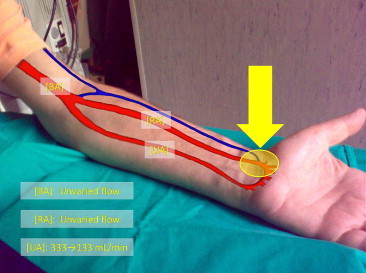

Fig. 3.

Doppler dynamic test: manual compression of the distal AVF [UA]: ulnar artery; [RA]: radial artery; [BA]: brachial artery.

Dynamic Doppler studies were performed to determine whether surgical ligation of one of the fistulas could be performed to improve the patient’s clinical symptoms. Each of the AVFs was manually compressed, and the hemodynamic effects of this maneuver were assessed. Compression of the proximal AVF did not produce any substantial changes in arterial or venous flow in the left forearm. In particular, it did not increase the flow through the distal AVF to values suitable for use in dialysis (Fig. 2). In contrast, compression of the distal AVF caused a marked change in the Doppler trace of the UA, which became triphasic (high-resistance), and a reduction of the UA flow rate from 333 to 133 mL/min (Figs. 3 and 4). The patient was therefore scheduled for surgical ligation of the distal radio-cephalic AVF.